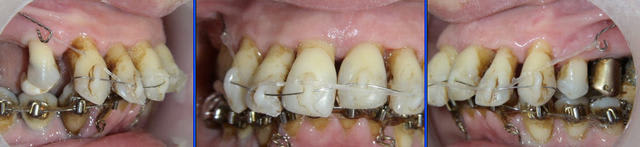

Voici le cas à 3 semaines. Les diastèmes sont complètement fermés.

J’ai rajouté une traction au niveau des incisives centrales. Il y a donc pour le même groupe de dents deux tractions, une au niveau des canines et une autre au niveau des centrales.

Voyez la qualité de la cicatrisation au niveau de l’émergence de la ligature de la muqueuse inférieure.